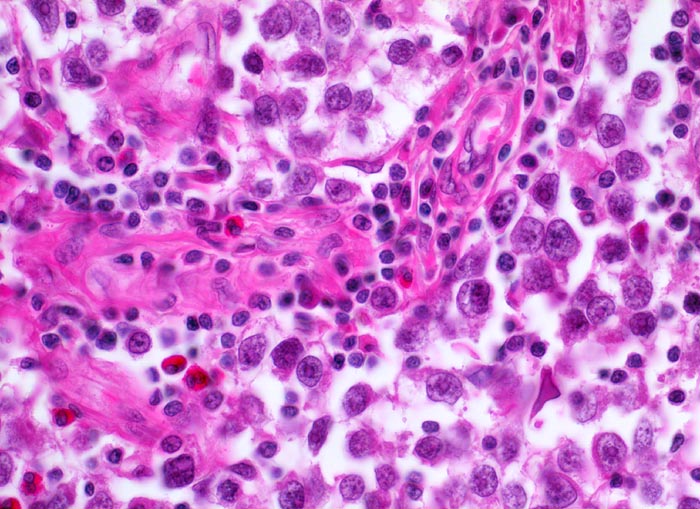

Seminom des Hodens

Beschreibung

Makroskopisch aus mehreren Knoten bestehender weisser Tumor von 2cm Durchmesser.

Der Patient suchte den Arzt wegen einer schmerzlosen Hodenvergrösserung auf.

Histologie

400